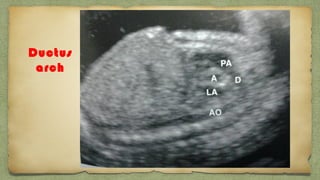

Aortic arch

Ductus

arch